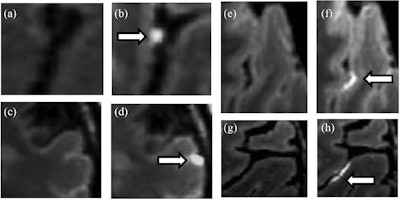

Images show examples of leptomeningeal enhancement in relapsing-remitting MS subjects as detected by 3D fluid-attenuated inversion-recovery (FLAIR) sagittal sequences at 7-tesla MRI. Pre- (a, c, e, g) and postcontrast (b, d, f, h) images showing representative foci of leptomeningeal enhancement arrows. Characteristic nodular leptomeningeal enhancement foci (b, d; arrows) found within a sulcus (b) and at the pial surface (d). Spread/fill leptomeningeal enhancement focus examples (f, h), with contrast layering within the sulcal depth (arrows). Images courtesy of Brigham and Women’s Hospital and the Multiple Sclerosis Journal.As one might expect, 7-tesla MR images revealed leptomeningeal enhancement in 20 MS patients (67%), compared with only one leptomeningeal enhancement (7%) among the healthy controls. The researchers also observed a total of 54 foci of leptomeningeal enhancement among those 20 subjects for a mean of 2.7 (± 1.5; range 1-6) foci per patient.